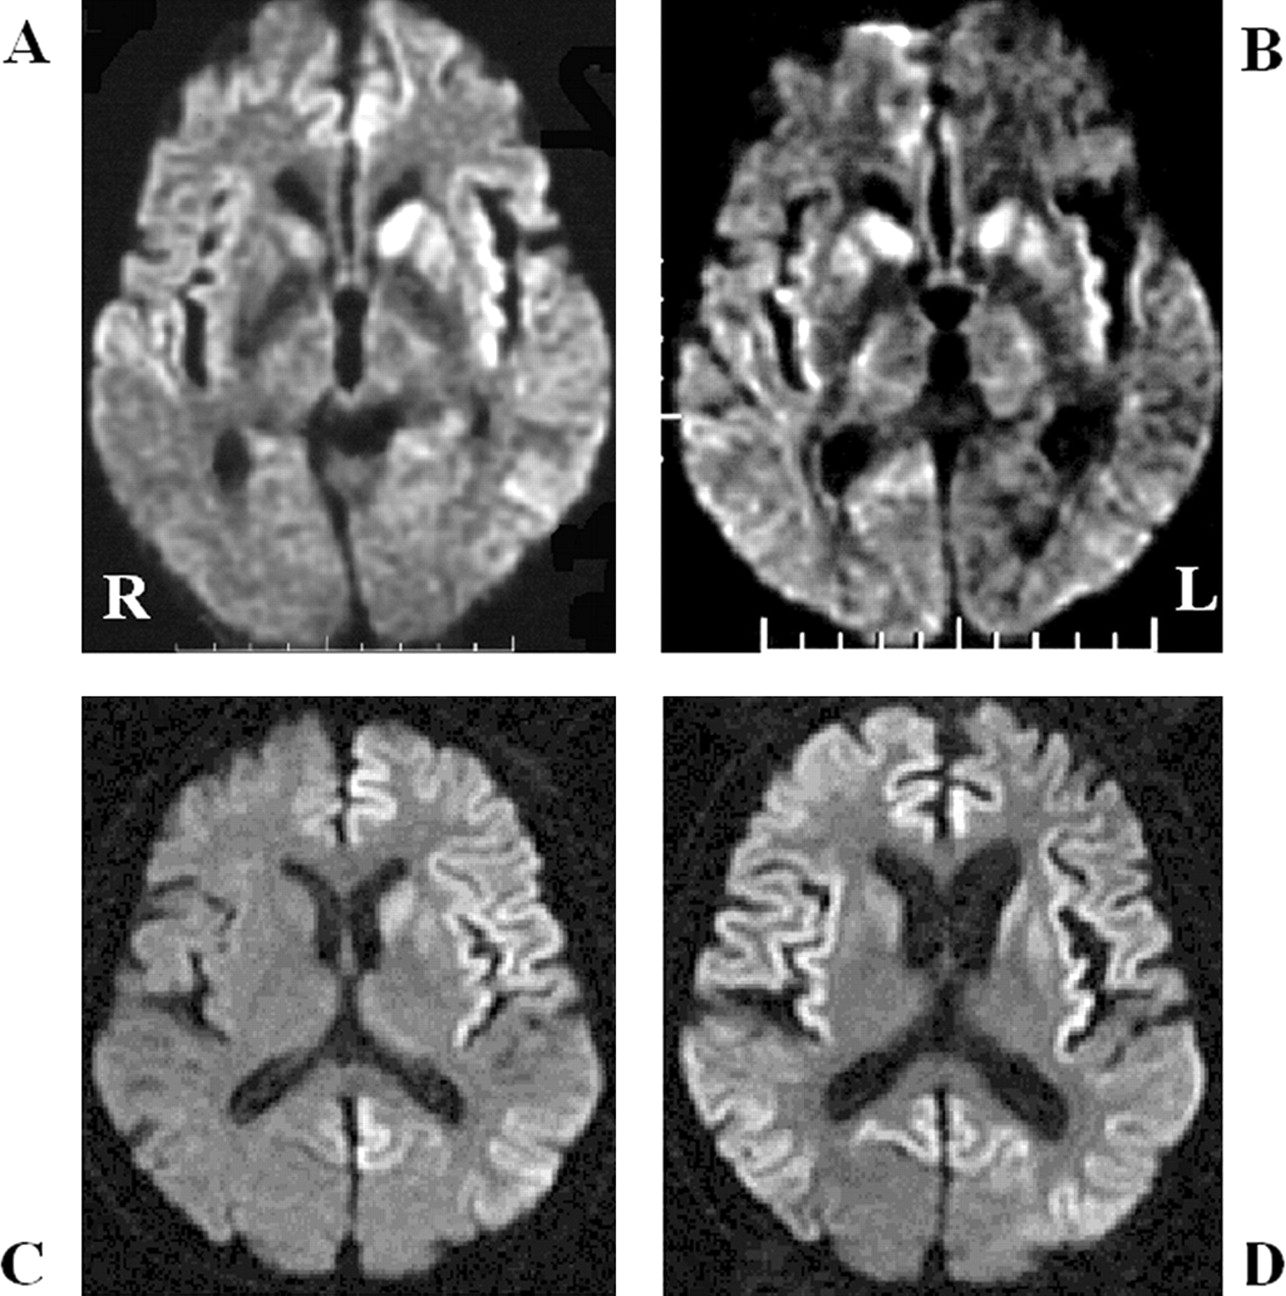

酒后驾驶是在26日检查库贾氏症患者发病后3到25周平均持续时间为10.7周。24库贾氏症患者表现出高强度脑损伤的驾车考试。两个观察者,醉酒驾车的库贾氏症诊断的敏感性为92.3%。interobserver协议率为100%。3例(12.5%)显示只在尾状头和硬膜损伤,10例(41.7%)患者显示线性损伤只有在大脑皮层,和11例(45.8%)患者显示病变基底神经节和大脑皮层(图1)。其中,只有三个病人(12.5%)显示,丘脑病变。没有病人显示高强度在小脑病变。高强度损伤在驾车之前出现脑萎缩。病变包括纹状体初并不总是对称的但是后来对称(图2),尽管对称的纹状体病变是众所周知的在库贾氏症。11在某些情况下,高强度损伤与连续驾车并不总是进展的疾病,而有时信号强度降低了疾病进展的一些病变。在某些情况下,皮质高信号强度不同,解剖分布(图3)。在终端阶段与深刻的脑萎缩,高强度损伤变得不清楚。T2I DWI-examined 26日在23日检查病人,但T2I扫描被排除在外,因为低质量由于运动构件。一位观察家认为11 22患者阳性(50.0%),而另一个观察者认为8阳性(36.4%)。interobserver协议率为68.2%,低于酒后驾车(p< 0.005)。在这两个观察者,醉酒驾车是比T2I更敏感(p一个观察者,< 0.005p另一个观察者p < 0.0005)。天赋是17 26患者的检查。一位观察家认为10 17例阳性(58.8%),和另一个观察者认为7是积极的(41.2%)。interobserver协议率为82.4%,也低于酒后驾车(p< 0.05)。醉酒驾车是比天赋更敏感(p一个观察者,< 0.01p另一个观察者p < 0.0005)。我们在图4一个例子中,只有醉酒驾车可以检测高强度异常病变。

高强度醉酒驾车是符合我们的标准观察到病变的疾病控制的病人。一位观察家认为,一个69岁的女人,隐球菌脑膜脑炎和一个60岁的女人区间形式的CO中毒是误判。另一个观察者认为,一名48岁的女性与单纯疱疹脑炎和47岁的酒精性脑病是误判。两个观察者,假阳性率6.3%,interobserver协议率为87.5%。没有高度CJD-suspected证明高强度损伤的病人。醉酒驾车的敏感性为92.3% (95% CI 74.8 - 99.5%)和特异性93.8% (95% CI 79.2 - 99.2%)。